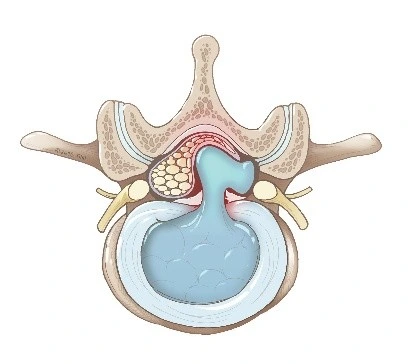

An intervertebral disc lies between the bones (vertebrae) of the spine and acts as a cushion and shock absorber. In a bulging disc the outer rim of the disc (the annulus) protrudes outward but remains intact; in a herniated disc the inner gel‑like core (nucleus) pushes through a tear or weakness in the outer rim.